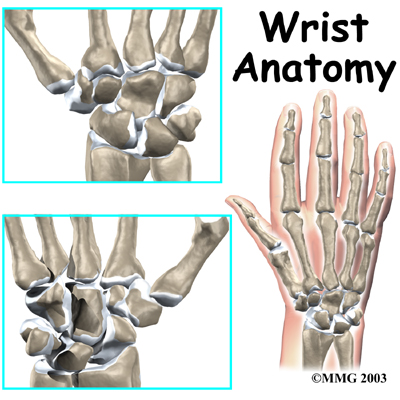

The anatomy of the wrist joint is extremely complex, probably the most complex of all the joints in the body. The wrist is actually a collection of many bones and joints. These

bones and joints let us use our hands in lots of different ways. The wrist must be extremely mobile to give our hands a full range of motion. At the same time, the wrist must provide the strength for heavy gripping.

There are 15 bones that form connections from the end of the forearm to the hand. The wrist itself contains eight small bones, called:

These bones are grouped in two rows across the wrist. The

is where the wrist creases when you bend it. Beginning with the thumb-side of the wrist, the proximal row of carpal bones is made up of the scaphoid, lunate, and triquetrum. The second row of carpal bones, called the:

meets the proximal row a little further toward the fingers. The distal row is made up of the trapezium, trapezoid, capitate, hamate, and pisiform bones.

The proximal row of carpal bones connects the two bones of the forearm, the radius and the ulna, to the bones of the hand. The bones of the hand are called the

metacarpal bones. These are the long bones that lie within the palm of the hand. The metacarpals attach to the phalanges, which are the bones in the fingers and thumb.

One reason that the wrist is so complicated is because every small carpal bone forms a joint with the bone next to it. This means that what we call the wrist joint is actually made up of many small joints.